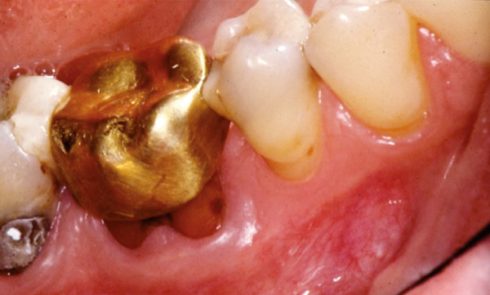

CAS 1 Motif de la consultation. Patient de 51 ans qui est venu consulter car il avait découvert une tumeur...